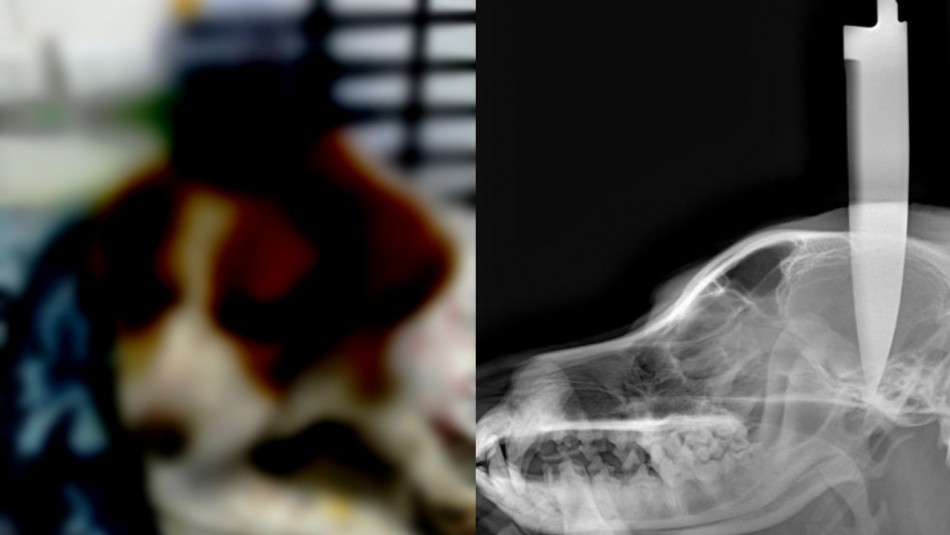

Sobre este caso, el veterinario José Quetalpillan, dijo que “Baby” fue llevado por su dueña hasta la consulta veterinaria y que al atenderlo por la grave lesión, se encontraba “consciente” pero “adolorido”.

“Pudimos constatar una lesión gravísima en su cráneo por un cuchillo aproximadamente de 20 centímetros, que atravesaba el hueso temporal. El paciente llegó consciente, alerta, sí un poco adolorido”, comentó.

Se reseña en el citado medio que el paciente fue sometido a radiografías y exámenes para poder considerar una operación para quitar el arma. Este jueves, será atendido por un neurocirujano y se verá si es factible poder quitar el cuchillo.